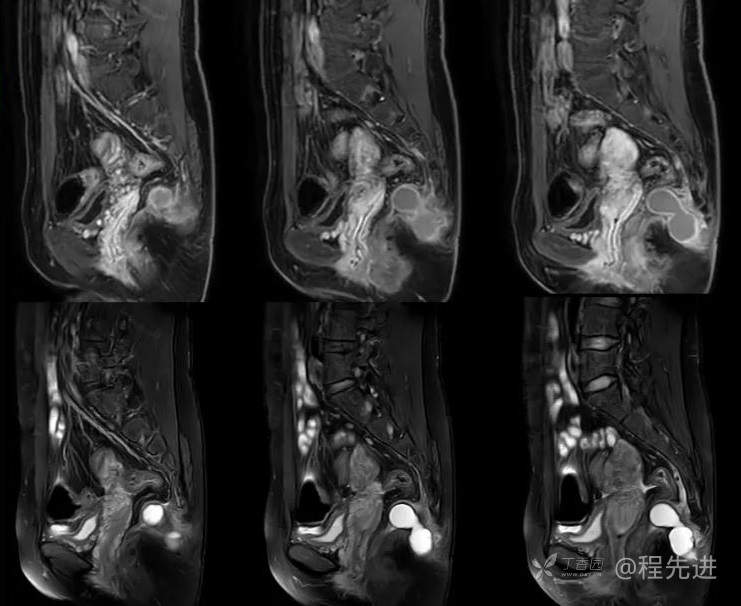

简要病史:3个月前无明显诱因出现骶尾部疼痛,胀痛为主,程度轻微,B超发现肿块3天。

体格检查:脊柱生理曲度存在,无侧弯,无压痛,活动可。尾骨尖右侧旁开2-3CM压痛。